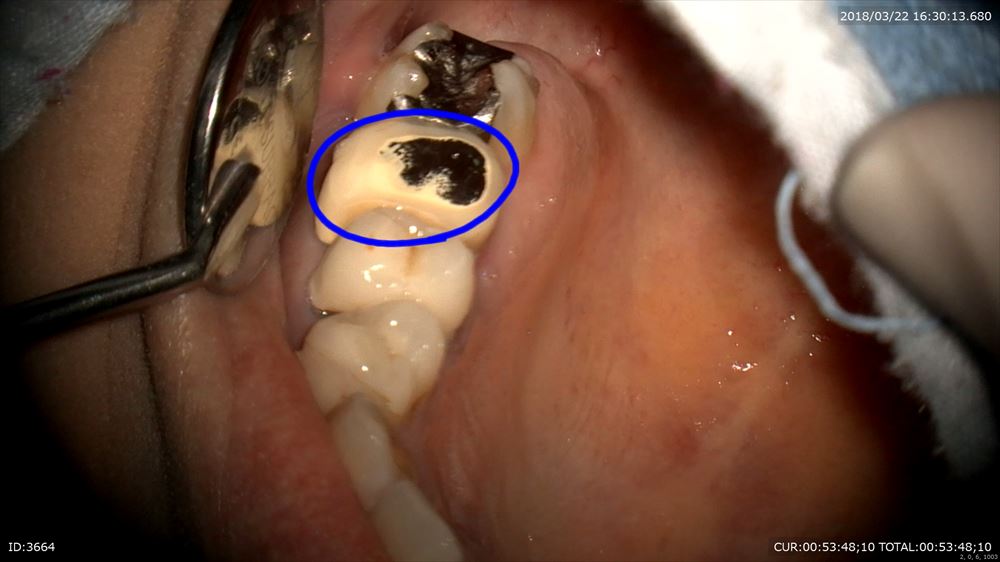

歯科ドックで大きい根尖病変が発覚。この歯です。力の影響もありそう。

丁寧に被せ物を外して、ここからラバーダム

CTで歯の又の部分に影がありました。こういう時は破折が多いのです。ここ!

やはりありました。